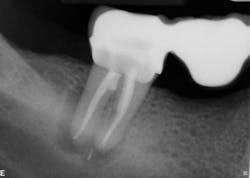

The second case involves a patient with tooth no. 19 having substantial furcation damage and moderate-sized apical periodontitis (figure 3).

Treatment included a two-visit approach, with two weeks in interim calcium hydroxide therapy.